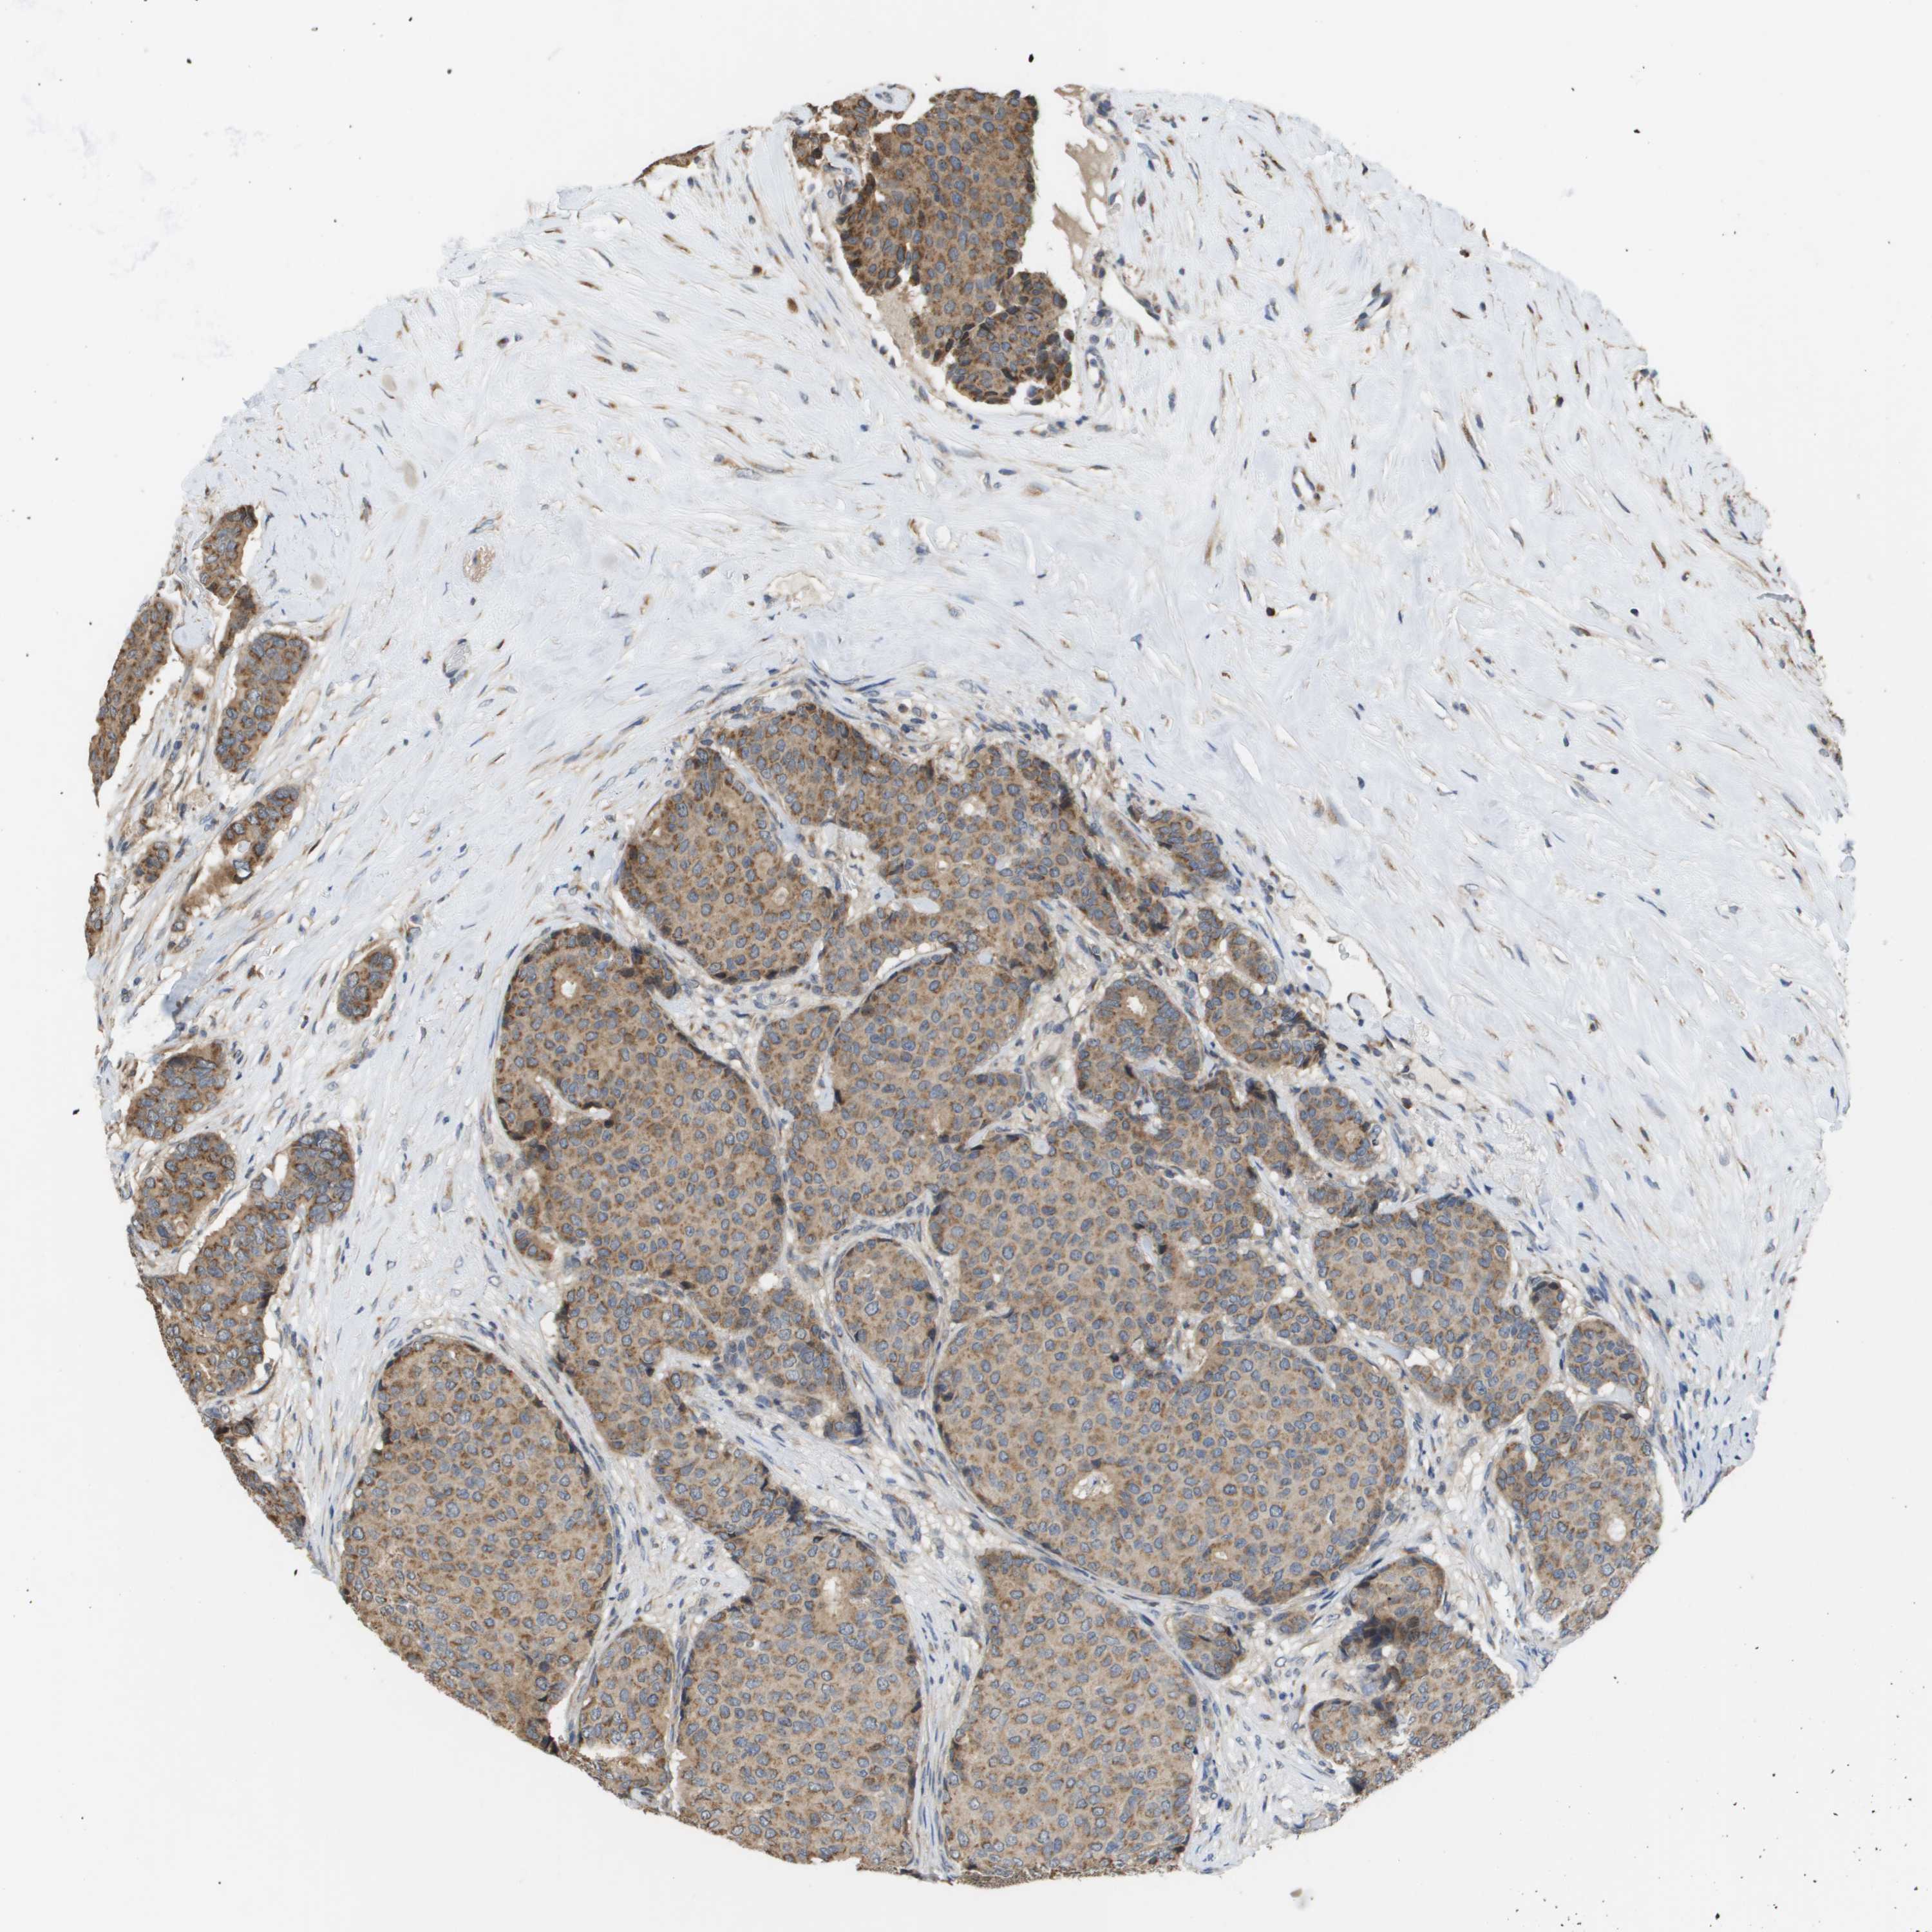

CANCER BREAST CANCER Show tissue menu

BRCA TCGA BRCA VALIDATION PROTEIN EXPRESSION

Breast cancer

Human cancer